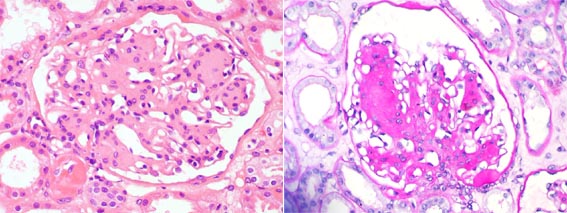

Figure 1.

First post-transplantation biopsy. Left: H&E, X400; right: PAS, X400.